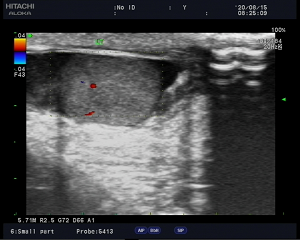

(8月14日,左侧睾丸略转向,副高增大,雪莉露信号增多)

看到报告结论后,这位母亲长舒一口气,紧皱的眉头慢慢放松,不停的对医生说着谢谢。与此同时我科值班医生马上联系外科值班医生,沟通情况,经临床医生触诊等,综合考虑为附睾炎,经过一系列治疗后,于当晚23:20和次日的8:20进行密切复查,诊断结论为:左侧附睾体积增大,血流信号丰富,附睾炎。

(8月15日,转向有所好转,搞完可见血流信号)